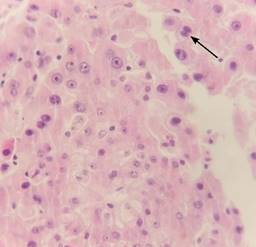

Reporte histopatológico de implante hepático: neoplasia maligna moderadamente diferenciada, consistente en carcinoma hepatocelular sarcomatoide (Figuras 4 y 5).

Figura 4: Se observan células hepáticas de aspecto neoplásico, las cuales muestran núcleos heterogéneos con nucléolos prominentes con citoplasma amplio eosinófilo. Estos grupos celulares en algunas áreas se intercalan con células fusiformes con atipia caracterizada por núcleos pleomórficos y mitosis atípicas (señalados con una flecha).